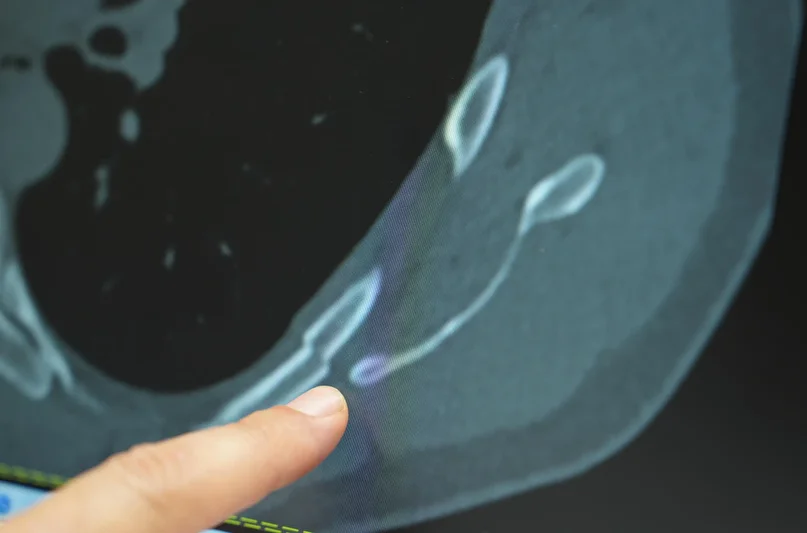

Göğüs ağrısı deyince akla yaşlılar gelir ama son dönemde gençlerde de öksürük sonrası kaburga kırıkları artış gösteriyor. Medipol Bahçelievler Hastanesi’nden Göğüs Cerrahisi Uzmanı Prof. Dr. Güven Sadi Sunam, genç yaşta görülen kaburga kırıklarının ardındaki gizli tehlikeleri ve korunma yollarını paylaştı.